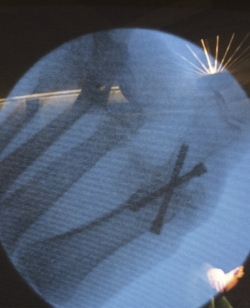

La posición de la artrodesis se determina utilizando la proyección de perfil con el Fluoroscan®, para evitar subluxaciones de la misma. Es con la visión de perfil cuando se colocan las agujas de Kirschner para los tornillos canulados y, después, se comprueba que la posición es correcta con la visión de frente. De forma percutánea, se colocan 2 agujas de Kirschner, una desde la primera falange y otra desde el metatarsiano en forma de X, cruzándose al nivel de la articulación (Figura 4). Es útil comprimir los dos huesos con la mano mientras se pasan las agujas.

Figura 4. Los 3 portales necesarios para la artrodesis percutánea de la articulación metatarsofalángica del primer dedo. El portal más proximal y el más distal se utilizan para la introducción de los tornillos canulados.